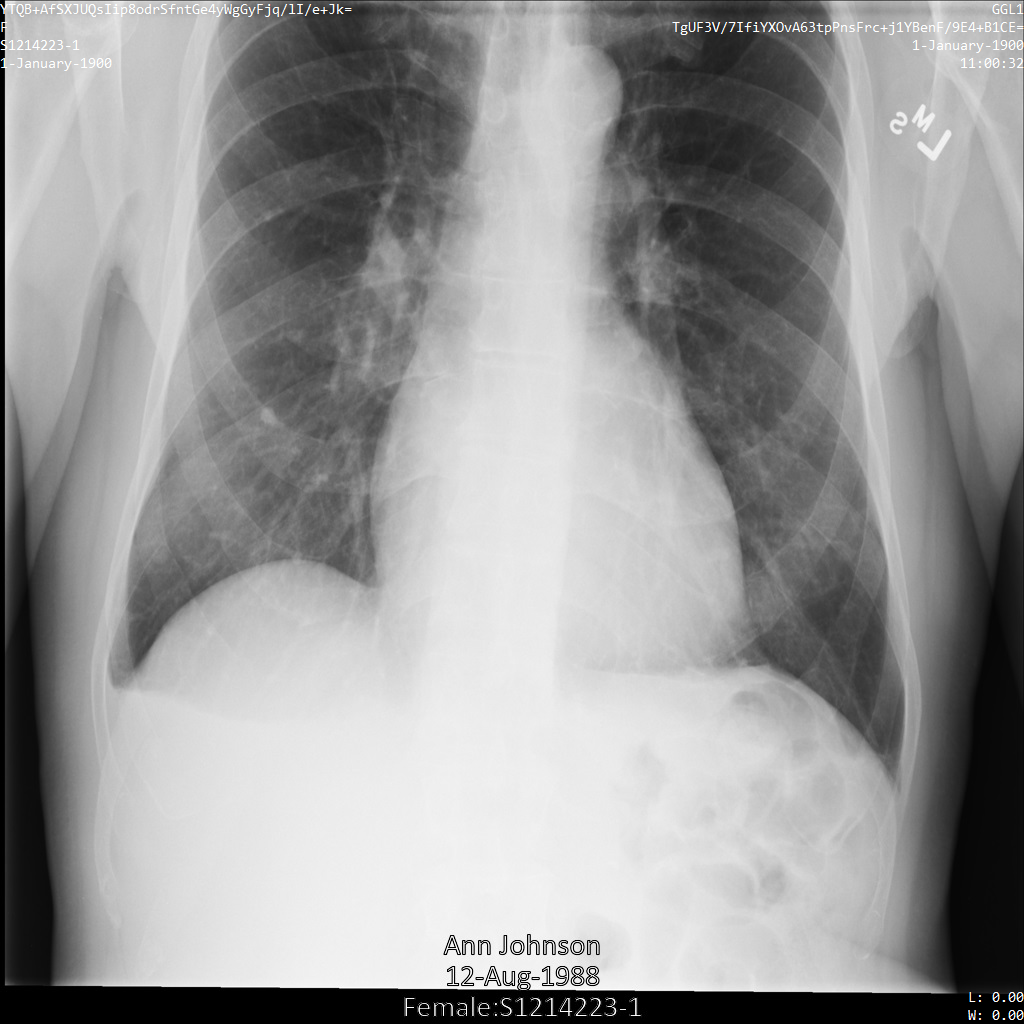

En cada una de las siguientes secciones, se proporcionan ejemplos de cómo desidentificar datos de DICOM mediante varios métodos. Se proporciona un resultado de la imagen desidentificada en cada muestra. En cada muestra, se usa la siguiente imagen original como su entrada:

Puedes comparar la imagen de salida de cada operación de desidentificación con esta imagen original para ver los efectos de la operación.

En la siguiente imagen, se muestra una radiografía sin ocultamiento de un paciente:

Después de enviar la imagen a la API de Cloud Healthcare mediante la opción REDACT_SENSITIVE_TEXT, la imagen aparece de la siguiente manera:

Puedes ver que ocurrió lo siguiente:

- Se ocultó el elemento

PERSON_NAMEen la esquina inferior izquierda de la imagen - Se ocultó el elemento

DATEen la esquina inferior izquierda de la imagen

El sexo del paciente no se ocultó porque no se considera texto sensible de acuerdo con los Infotipos de DICOM predeterminados.